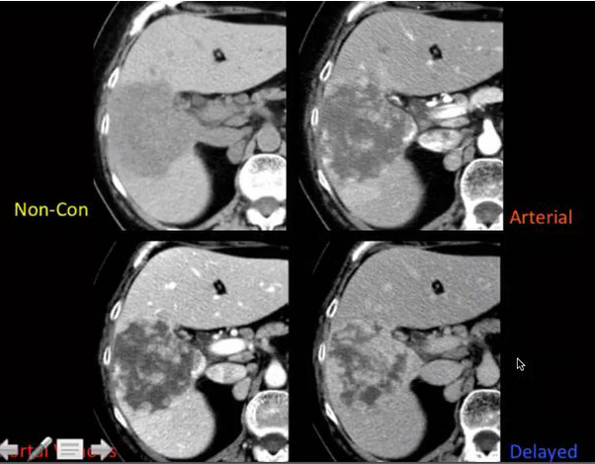

CT tech calls you to the scanner to console a pt who the tech just told has a horrible liver cancer. What is your next step?

get delayed images (10-20 min). this is most likely a cavernous hemangioma

You think that the following is a hemangioma in a fatty liver, but the mid-level provider doesn’t believe you. The patient has abandoned pacer leads and can’t get an MRI. What is your next step?

Tagged RBC scan to look for hemangiomas